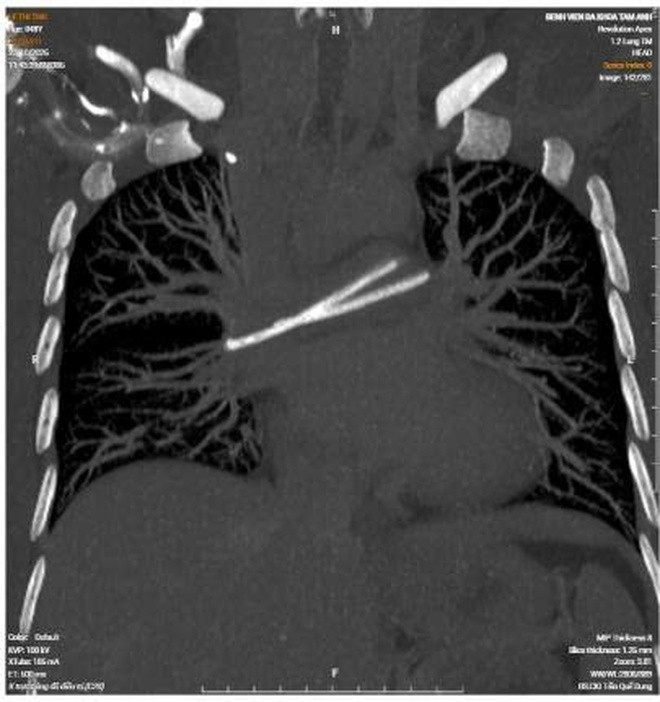

Hình ảnh dị vật chèn ngang động mạch phổi qua phim chụp CT và X-quang

Mới đây, bệnh nhân đi khám tầm soát và chụp CT ngực tại một cơ sở y tế tư nhân thì phát hiện dị vật trong tim, nằm vắt ngang tại vị trí động mạch phổi hai bên. Sau đó, bệnh nhân quay về bệnh viện đã điều trị ung thư trực tràng để tiếp tục thăm khám và được tiến hành chụp X-quang ngực.

Kết quả ghi nhận mất liên tục thân catheter, xác định catheter đã bị đứt. Phần buồng truyền dưới da vẫn còn tại vị trí dưới xương đòn phải, phần đầu còn lại đã di chuyển về tim và nằm trong động mạch phổi.